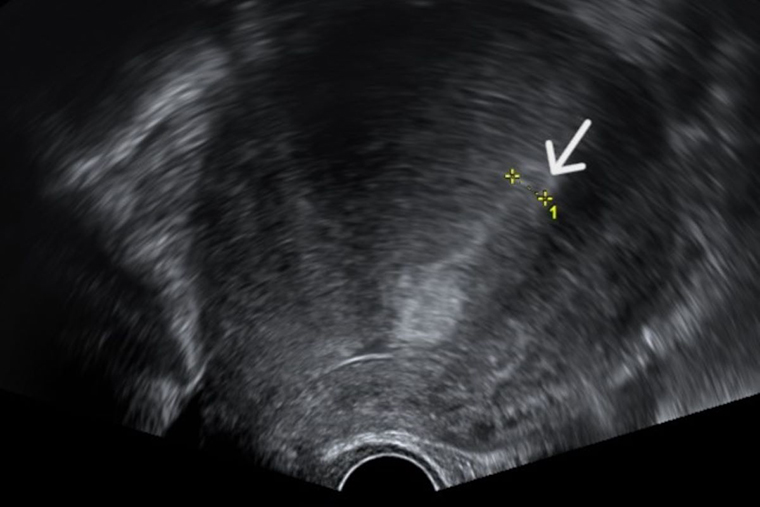

▲透過超音波檢查,發現子宮內膜增生異常的情形。(圖/台北慈濟醫院提供)

【NOW健康 吳思奕/新北報導】1名60歲的吳女士因為停經後仍有不定期出血的情形,因此一直持續在台北慈濟醫院進行追蹤檢查。日前在某次回診中,透過超音波檢查發現子宮內膜厚度異常增生,遂決定接受子宮內膜搔刮術進行採樣。經手個案的台北慈濟醫院婦產部醫師邵芷萱說,在手術中發現了吳女士的子宮中有一塊肉瘤,若不及時處理,很有可能會病變為子宮內膜癌。因此在與吳女士討論後,決定以摘除子宮的方式根除病灶。術後吳女士不再受異常出血困擾,生活品質大幅提升。